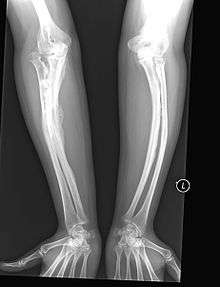

Type V

Having the same clinical features as Type IV, it is distinguished histologically by "mesh-like" bone appearance. Further characterized by the "V triad" consisting of a) radio-opaque band adjacent to growth plates, b) hypertrophic calluses at fracture sites, and c) calcification of the radio-ulnar interosseous membrane.[12]

OI Type V leads to calcification of the membrane between the two forearm bones, making it difficult to turn the wrist. Another symptom is abnormally large amounts of repair tissue (hyperplasic callus) at the site of fractures. Other features of this condition include radial head dislocation, long bone bowing, and mixed hearing loss.

At least some cases of this type are caused by mutations in the IFITM5 gene.[9]